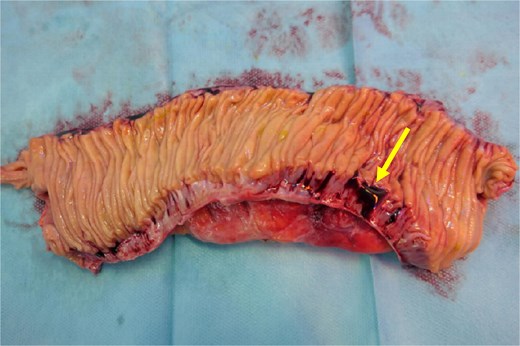

Intraoperatively, a purulent peritonitis was observed, along with an inflammatory, fibrin-covered conglomerate of the small bowel in the lower abdomen. After adhesiolysis, a segment of the distal jejunum ⁓30 cm in length, exhibiting significant inflammatory changes, was identified, with surrounding markedly edematous and thickened mesentery, as well as a diverticulum on the mesenteric wall with suspected perforation into the mesentery. Additionally, multiple non inflamed diverticula, measuring up to 1.5 cm in diameter, were identified along the jejunum. A segmental resection of the inflamed small bowel was performed, followed by a side-to-side anastomosis. The specimen was opened anti-mesenterically in the operating room, allowing for macroscopic verification of the diverticular perforation from an intraluminal perspective (Fig. 2).

Cut open small bowel segment verifying the diverticular perforation (arrow) from an intraluminal perspective.